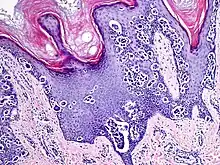

An acral nevus is a cutaneous condition of the palms, soles, fingers, or toes (peripheral body parts), characterized by a skin lesion that is usually macular or only slightly elevated, and may display a uniform brown or dark brown color, often with linear striations.[1]: 1726

Acral nevi may occur in all ethnic groups, but are more common in dark-skinned people. The acral nevus is a benign skin lesion that can occur at any age, but is generally noticed between 10 and 30 years of age. Both children and adults may be observed with this skin lesion. The prevalence of acral nevi increases directly with degree of skin pigmentation. In a study, palmar or plantar nevi were detected in 42.0% of black (50 of 119) vs 23.0% of whites (79 of 343). Palmar or plantar nevi of 6 mm diameter or larger were detected in 3.4% of blacks (4 of 119) vs 0.6% of whites.[2]

They are brown to dark brown in color and have linear streaks of darker pigmentation. Size is usually 7 mm or less, oval or spindle shaped, and well-demarcated. They become stable after an initial growth phase, and the number of lesions also decreases; a new lesion in middle-aged or elderly people should raise suspicion of acral lentiginous melanoma.